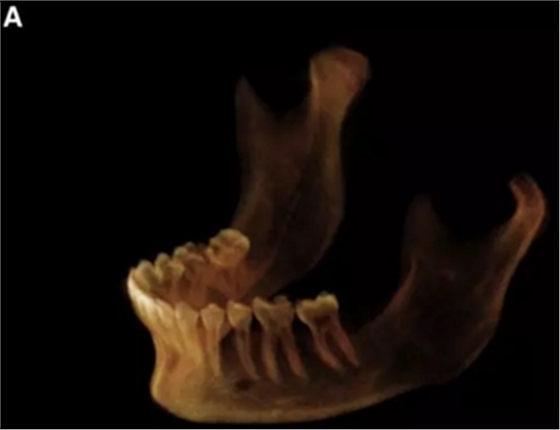

在輸出的3D模型上,使用體內(nèi)軟件(Anatomage,San Jose,Calif)將下頜骨以最小的間隔從顱骨上分離(圖5)用于保留下頜骨的咬合細節(jié),游離的下頜骨被保存(圖6,A)。同時,將沒有下頜骨的顱骨導出并保存(圖6,B)。

圖6. A,從整個3D模型上修剪的下頜骨; B,修剪的顱骨。